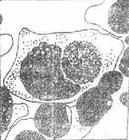

衣原體性結膜炎衣原體性結膜炎包括沙眼、包涵體性結膜炎、性病淋巴肉芽腫性結膜炎等。衣原體是介於細菌與病毒之間的微生物,可寄生於細胞內形成包涵體。衣原體目分為二屬。屬Ⅰ為沙眼衣原體,可引起沙眼、包涵體性結膜炎和淋巴肉芽腫;屬Ⅱ為鸚鵡熱衣原體,可引起鸚鵡熱。

①眼下穹隆、下瞼結膜刮片行及姬拇薩或碘染色找胞漿內包涵體。